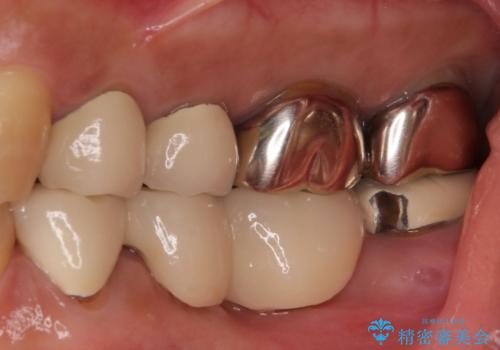

- 下顎の左右奥歯が痛みがあり、噛めないとのことで来院された患者様です。

左右ともに歯根が破折しており、抜歯が必要であったため、抜歯後にインプラント補綴治療を行うこととしました。

左上は当初治療予定ではありませんでしたが、クラウンの周りに汚れがたまっていることが気になってきたため、追加して治療を行うこととしました。